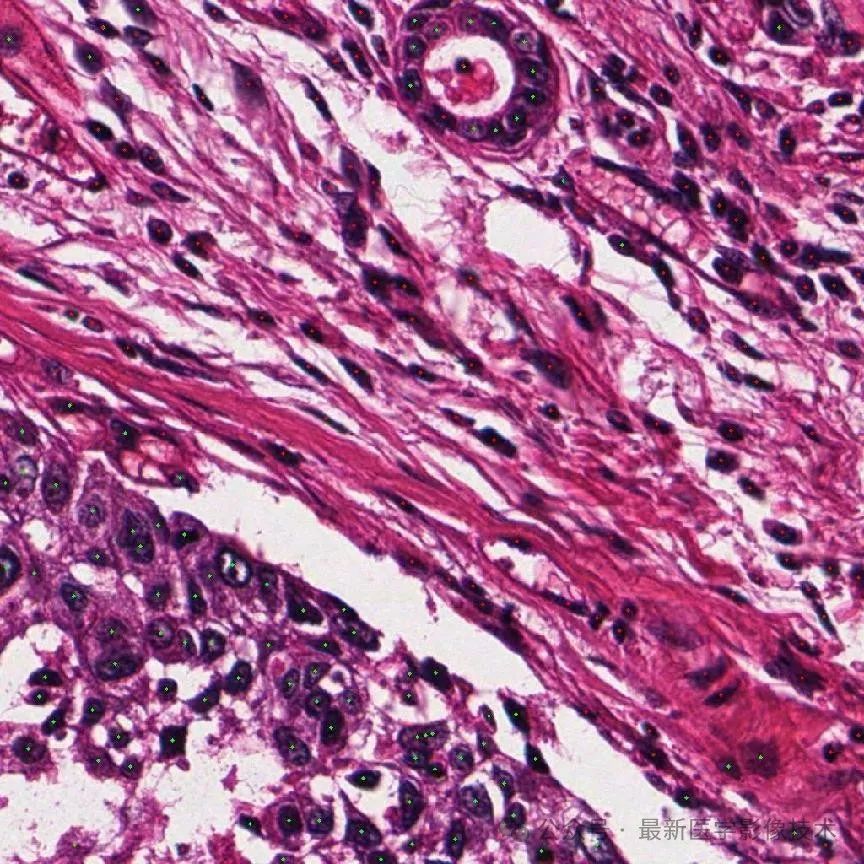

下图显示了示例的可视化。

数据集的每个样本都包含两个输入块和相应的注释。左侧显示了带有组织分割注释 y_l^t 的大 FoV 块 x_l,其中绿色表示癌症区域。右侧显示带有细胞点注释 y_s^c 的小视场块 x_s,其中蓝色和黄色点分别表示肿瘤和背景细胞。红色框表示 x_s 相对于 x_l 的大小和位置。请注意,对于每个样本,x_s 和 x_l 是重叠的,即 x_s 存在于 x_l 内部。然而,x_s 在 x_l 上的相对位置因样本而异。